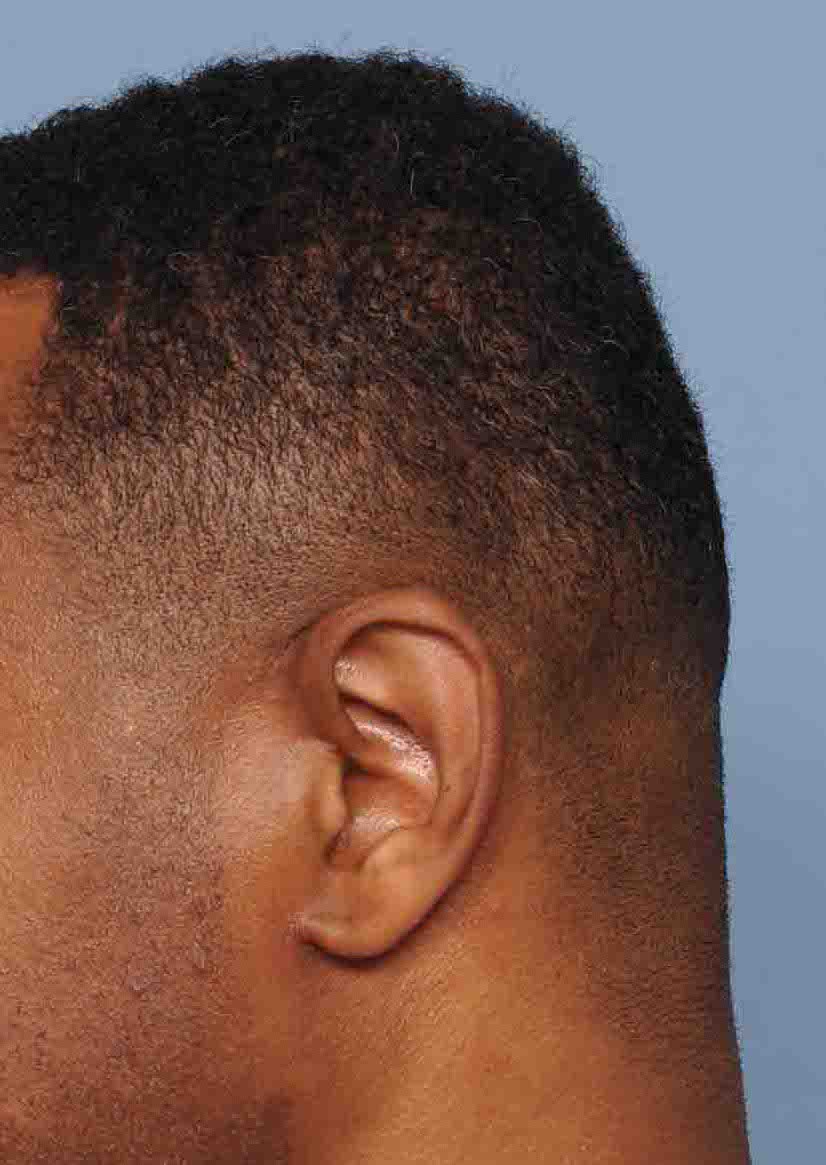

Young male seeking reduction of his convex sides of his head.

Head width reduction by posterior temporal muscle reduction through hidden postauricular incisions behind the ears.

Young male seeking reduction of his convex sides of his head.

Head width reduction by posterior temporal muscle reduction through hidden postauricular incisions behind the ears.